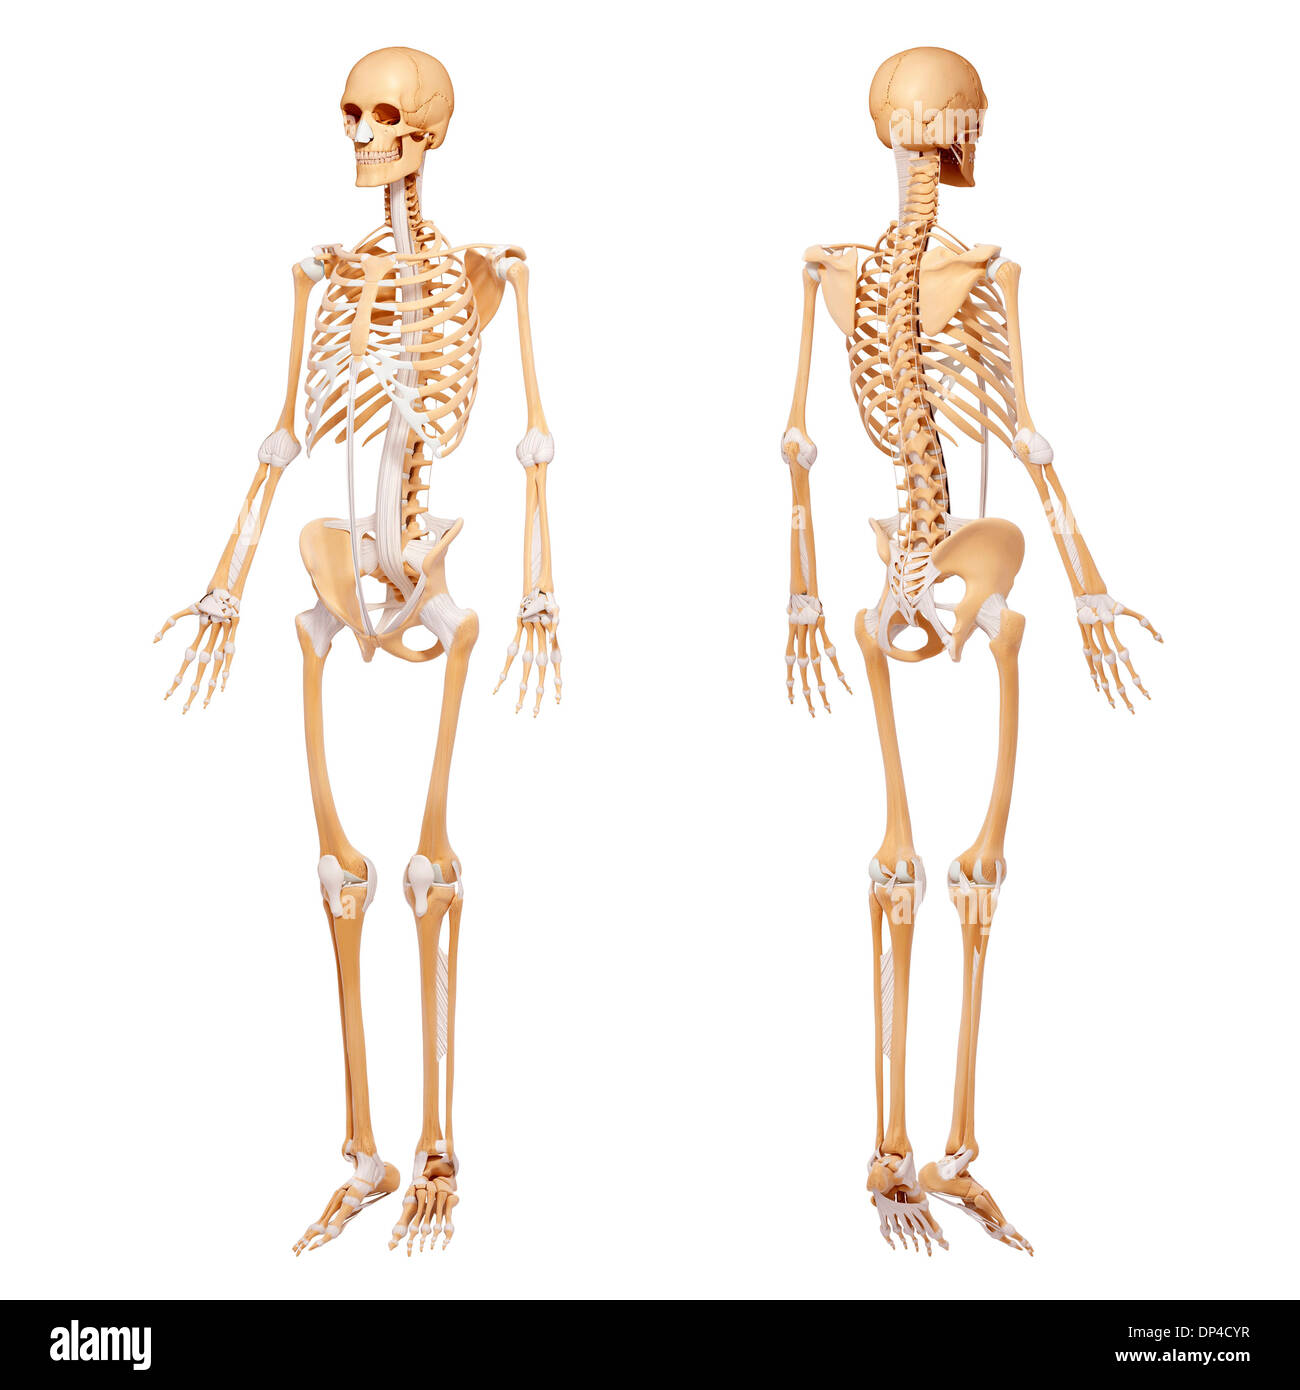

Human Skeleton, artwork Banque D'Imageshttps://www.alamyimages.fr/image-license-details/?v=1https://www.alamyimages.fr/human-skeleton-artwork-image65251531.html

Human Skeleton, artwork Banque D'Imageshttps://www.alamyimages.fr/image-license-details/?v=1https://www.alamyimages.fr/human-skeleton-artwork-image65251531.htmlRFDP4CYR–Human Skeleton, artwork